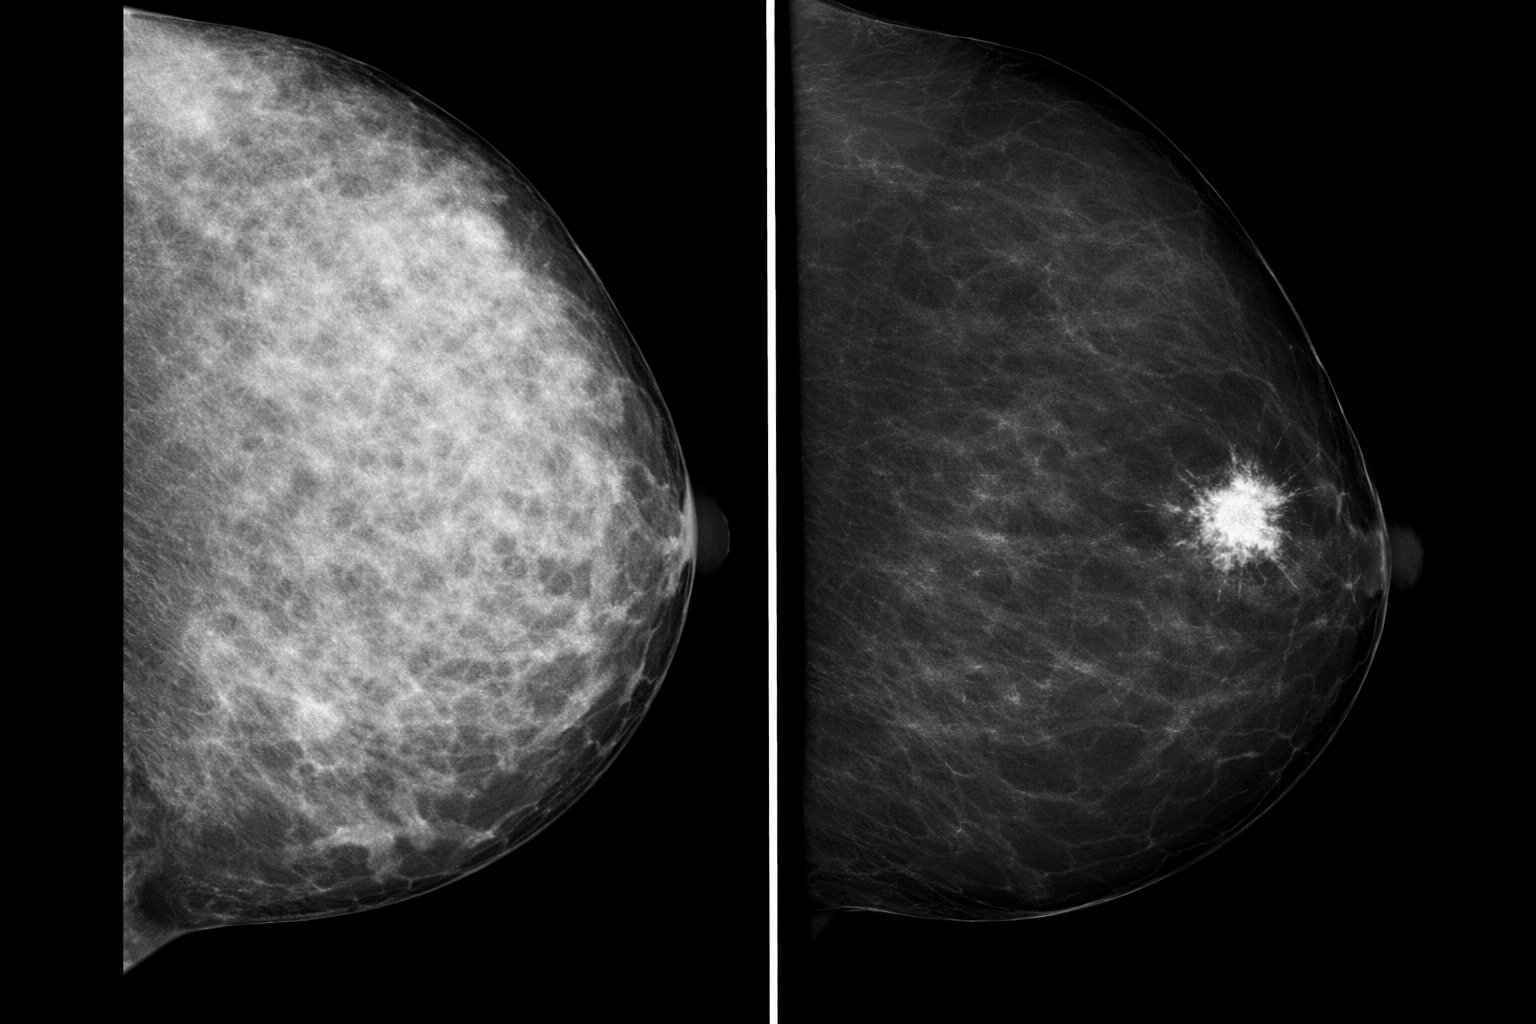

Senologia

Mammografia, ecografia e risonanza magnetica per la diagnosi e la prevenzione del tumore al seno.